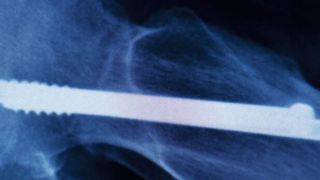

Eine neue Hüfte kann verlorene Lebensqualität zurückbringen. Doch mitunter kommt es auf dem Weg dahin zu Komplikationen. So erschweren infektiöse Bakterien die Einbindung des künstlichen Gelenks. Hier soll in Zukunft eine intelligente Beschichtung helfen, die genau dann aktiv wird, wenn Bakterien sich auf dem Implantat ausbreiten.

Augsburg, Hamburg, München – Über 150.000 Erstimplantationen von künstlichen Hüftgelenken wurden 2018 allein in Deutschland durchgeführt, heißt es im Jahresbericht des Endoprothesenregisters Deutschland. Die Implantation künstlicher Hüft- oder Kniegelenke gehört damit längst zum chirurgischen Alltag. Doch trotz fortschrittlicher Technik tritt nach wie vor ein Problem häufig auf: Infektionen in der Nähe der Prothese. Sie verzögern die Einheilung und können die Stabilität der Verbindung zwischen Endoprothese und Knochen dauerhaft beeinträchtigen. Darüber hinaus erhöhen sie für den Patienten das Operationsrisiko. „Erschwerend kommt hinzu, dass immer mehr Bakterien gegen gängige Antibiotika resistent werden“, sagt Dr. Christoph Westerhausen vom Lehrstuhl für Experimentalphysik I der Universität Augsburg. „Das zwingt uns zur Suche nach Alternativen.“

Eine solche Alternative könnte die neuartige Beschichtung sein, die das Forscherteam aus Augsburg, Hamburg und München nun entwickelt und getestet hat. Dabei handelt es sich um einen hauchdünnen Überzug aus diamantähnlichem Kohlenstoff, kurz DLC für diamond-like carbon.

DLC-Beschichtungen sind äußerst widerstandsfähig und zeichnen sich durch eine hohe Härte aus. Sie werden daher schon seit vielen Jahren immer dann eingesetzt, wenn Verschleiß und Abrieb minimiert werden müssen. Auch bieten Oberflächen aus DLC eine ausreichende Rauigkeit, sodass Knochenzellen gut daran haften. Das macht sie für sich genommen schon zu attraktiven Kandidaten für Implantate. Der Clou der neuartigen Beschichtung liegt aber woanders: „Wir haben sie gezielt mit Zinkoxid-Partikeln dotiert“, sagt Westerhausen. Die Zinkionen sind toxisch für Mikroorganismen und haben somit eine desinfizierende Wirkung.